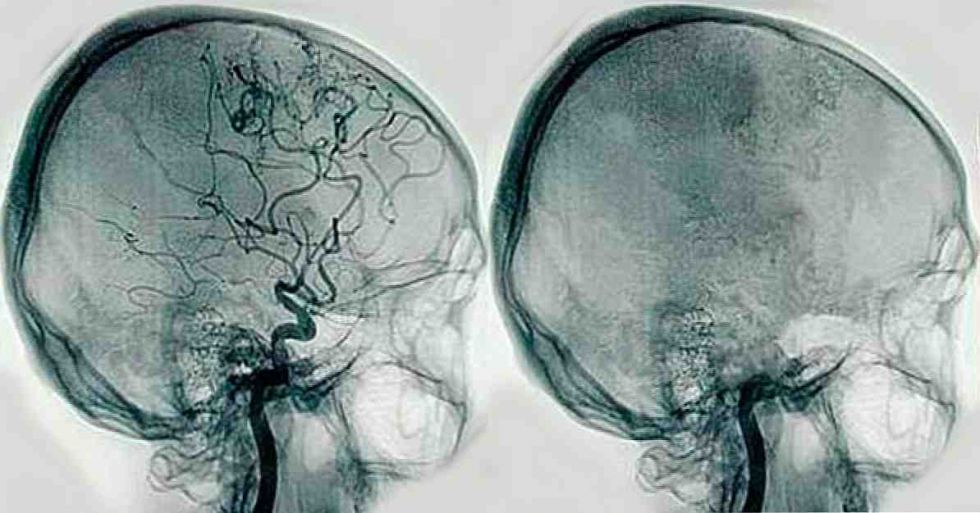

- Смерть мозга представляет собой необратимое прекращение всех его функций. Главные диагностические признаки: отсутствие активности полушарий, отсутствие мозговых рефлексов. При проведении электроэнцефалографии – тишина, никакой активности нейронов даже при искусственном раздражении. Также признаком смерти мозга является отсутствие признаков внутричерепного кровообращения, - добавляет специалист.

- Повреждение правого полушария может привести к чувству полета и легкости. Именно отсюда рассказы пациентов о том, что они будто бы висели в воздухе над своим телом. Ощущение встречи с духами и видения световых пятен можно объяснить повреждением левого полушария. А знаменитый туннель – следствие поражения затылочной коры, - поясняет врач.